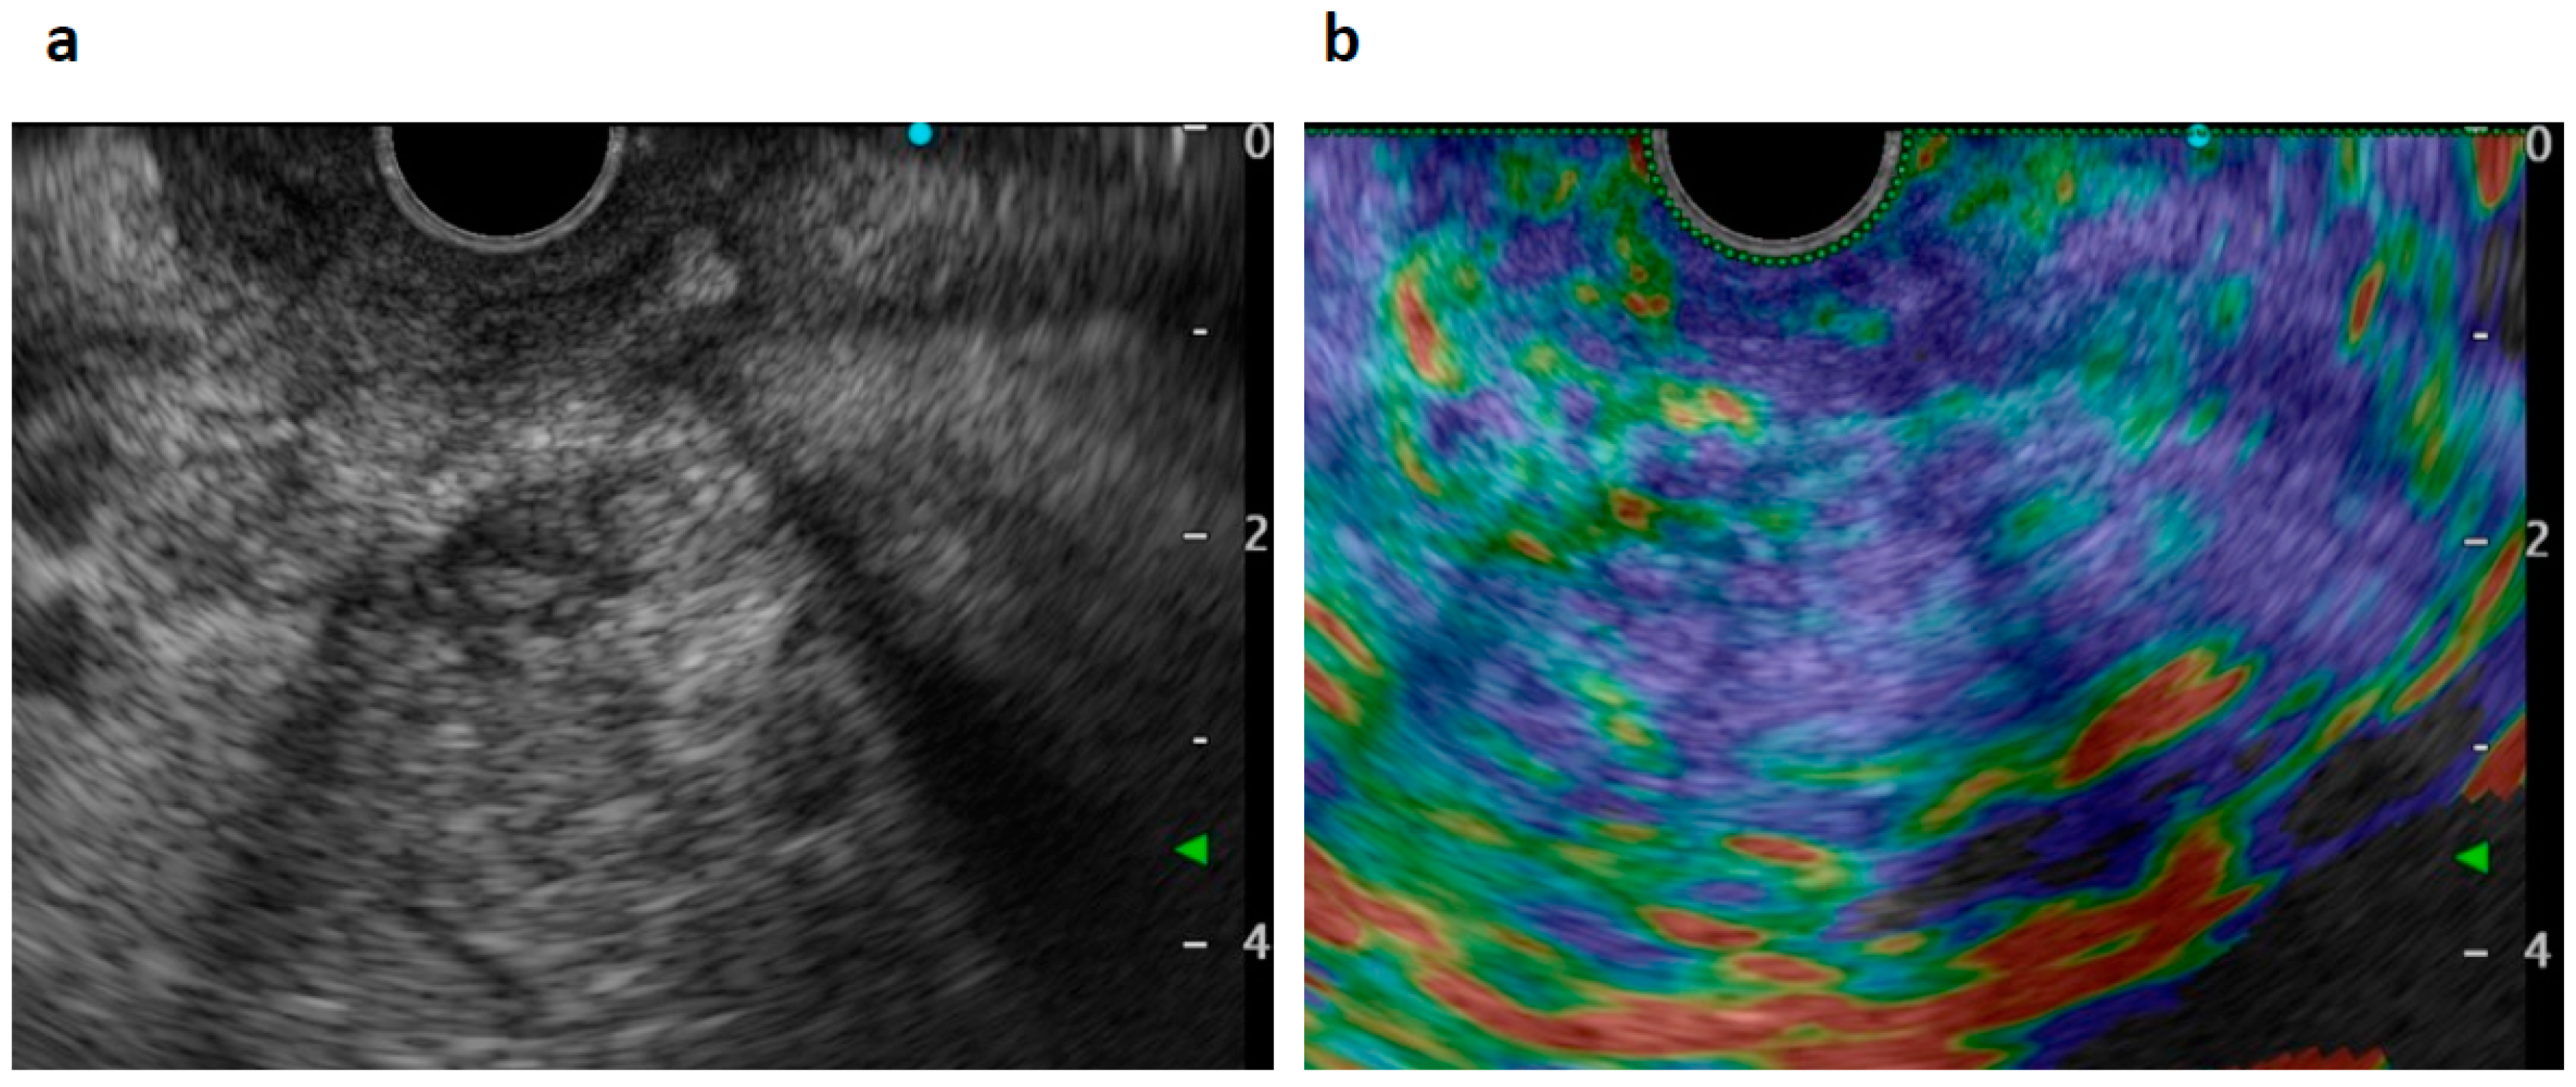

2. Case Presentation